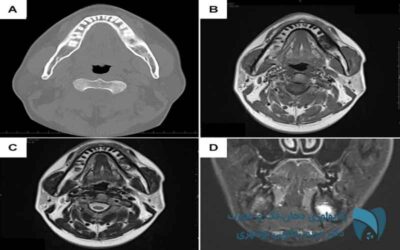

تصویربردای ام آر آی ; drbooshehri.com

ام آر آی؛ روش تشخیص دقیق و غیرتهاجمی

با استفاده از دستگاه تصویر برداری ام آر آی امکان عکس گرفتن از تقریباً همه بافت های بدن و...